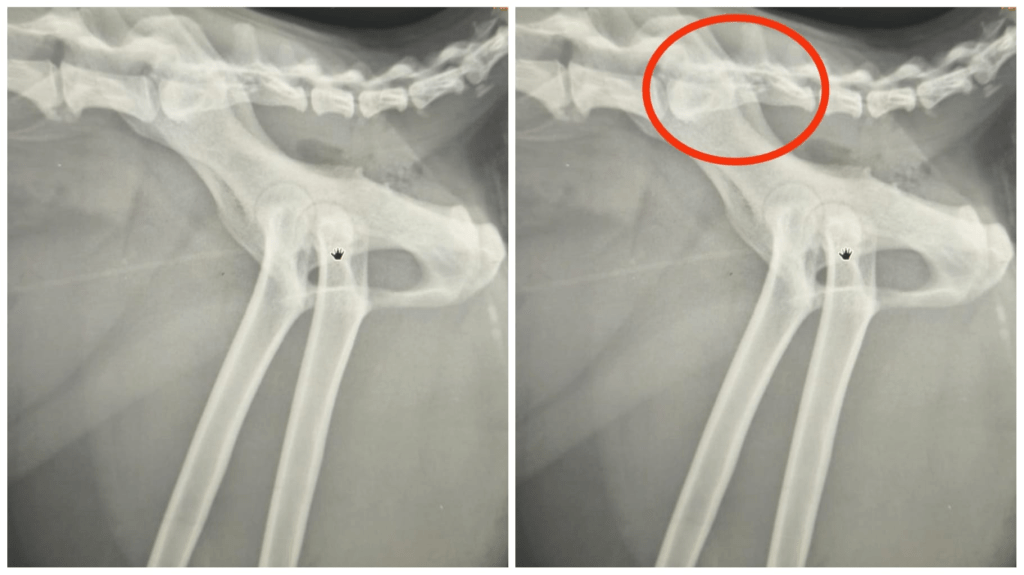

deformasyona uğrayan ayak parmakları da şekilsiz bir pati görünümüne sebebiyet verir. Radyografik incelemede ise; distal ekstremitelerde ilerleyici yeni kemik oluşumu ve topuk kemiğinin plantar yüzeyinde kemik tümörü (ekzostoz) oluşumu gözlenir. Bu ekzostozlar eklem ankilozuna (eklem oynaklığının azalmasına) yol açabilir. Yaygın osteopeni (kemiklerin zayıflaması) de lezyonlara eşlik eder. Bazı kedilerdeki klinik tablo çok şiddetli ağrılara sebep olurken kimisinde daha hafif şiddetli klinik tablolar gözlenebilir.